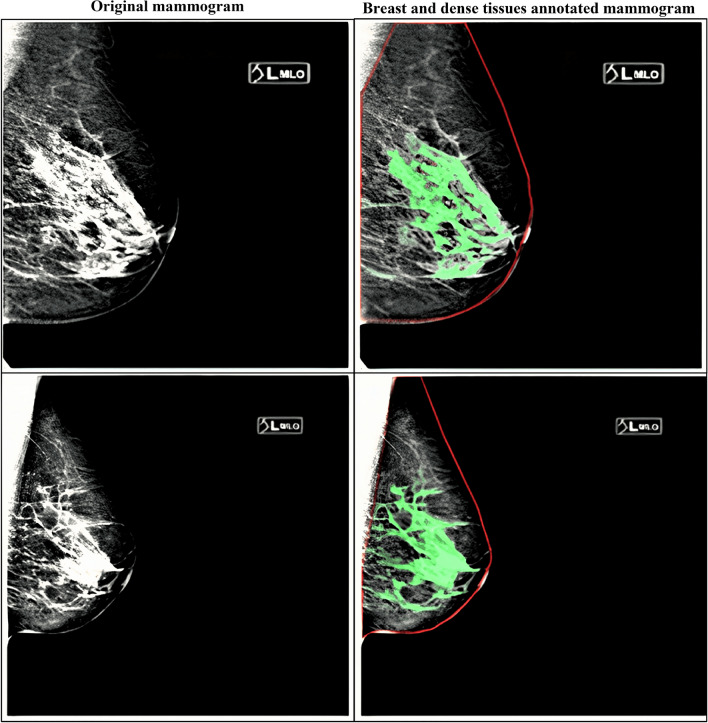

Based on BI-RADS categories, dense tissues are segmented using image-thresholding techniques14. With the variability in the image intensities and uncertainty in BI-RADS classification, the dense tissues are either over- or under-segmented. This study generated the dense-tissue binary masks using an in-house web-based interactive image segmentation tool developed in Python 3.6 and the Flask (https://flask.palletsprojects.com/en/2.0.x/) web framework under expert radiologist supervision. Figure 3 shows ground-truth annotations generated for the KUH dataset. The red contour line separates the breast area from other muscles, such as pectoral tissue in the MLO-view mammograms. The green pixels represent the dense (fibroglandular) tissues in the mammograms.

Figure 3.

Examples of generated ground-truth segmentation masks from the KUH development set for the breast and dense-tissue segmentation. We overlapped the segmented binary masks on the original mammogram.